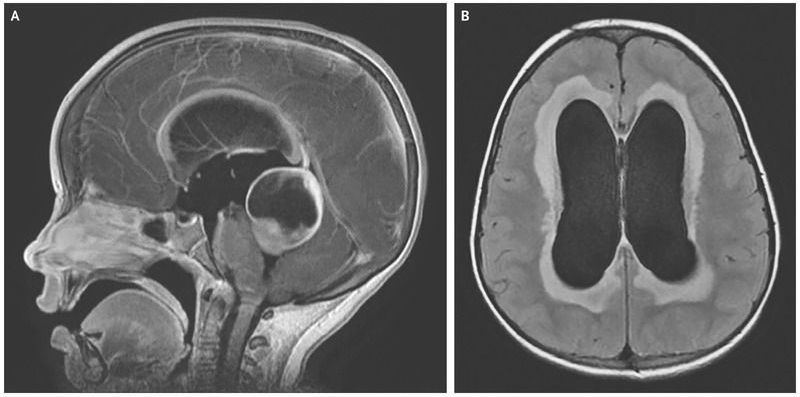

A 4-year-old girl with a 2-week history of progressive headache, nausea, vomiting, and irritability was brought to the emergency department. The patient was confused and combative. She had disconjugate gaze on extraocular examination and also had an unsteady, uncoordinated gait. Contrast-enhanced T1-weighted magnetic resonance imaging revealed a cystic mass measuring 3.4 cm by 3.9 cm by 4.4 cm in the quadrigeminal cistern, arising from the tectal plate and compressing the cerebral aqueduct (Panel A). Its presence resulted in obstructive hydrocephalus and bowing of the corpus callosum. Transependymal flow of the cerebrospinal fluid (CSF) was seen on the axial T2-weighted FLAIR (fluid-attenuated inversion recovery) sequences (Panel B). The patient underwent placement of an external ventricular drain, tumor resection, and endoscopic third ventriculostomy. Histologic examination of the tumor specimen led to a diagnosis of pilocytic astrocytoma. After surgery, the patient had complete resolution of her symptoms, and adjuvant chemotherapy was initiated. At follow-up 9 months after the surgery, the hydrocephalus had resolved without recurrence, and no further diversion of the CSF was required.